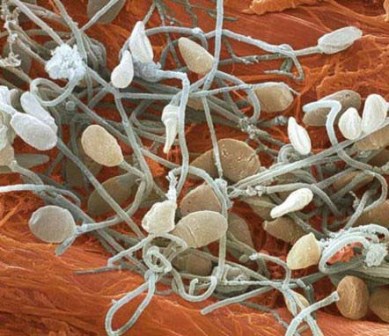

اسپرم